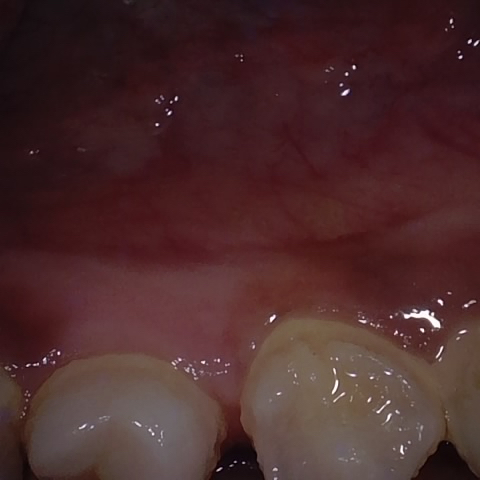

Annotated as "Good"